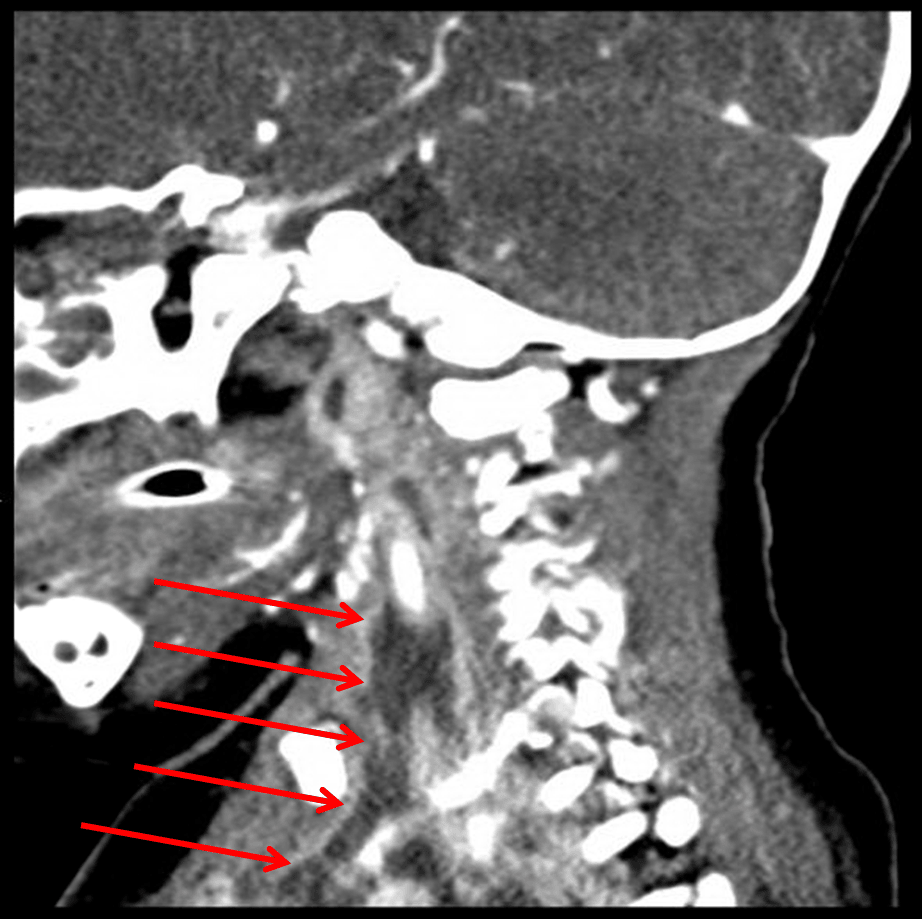

Red arrows: extension of infection through the carotid space.